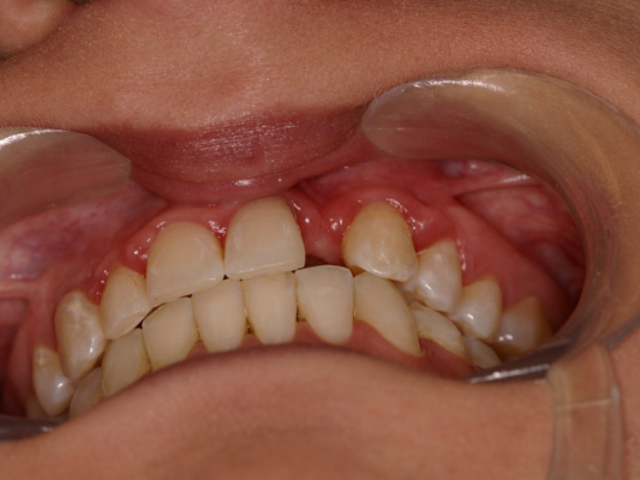

Case Study 14

Problem: This young man was hit by a car while riding his bike. He had multiple fractures in his jaw and three front teeth were fractured.

Plan: Our plan… his fractures were fixed. The trauma left a bony defect which was grafted as well as soft tissue VIP grafts. Placed three separate implants with guided surgery. Molded the tissue and placed Zirconium abutments with porcelain crowns.

A great young man with a confident smile.